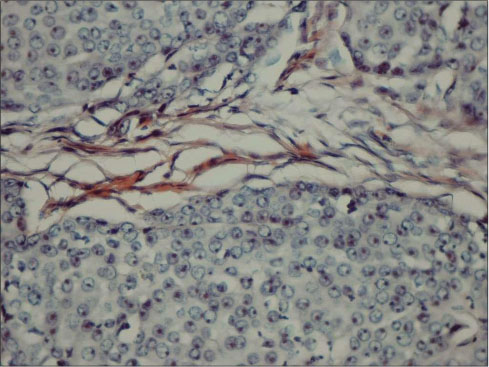

| Figure 1 Congo red staining in pleomorphic adenoma (×100)-positively stained eosinophils